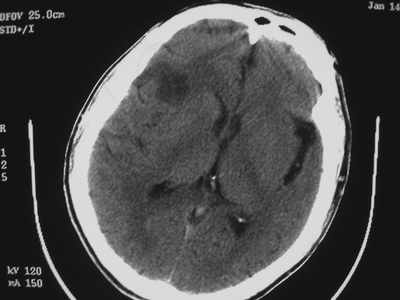

以下是引用卜一在2007-1-19 15:29:00的发言:[br]治疗前:1月14日右侧额叶皮质下低密度影,而治疗后:1月18日右侧阴影消失,新近出现左侧额叶侧脑室前角旁大片状低密度影,边缘模糊。支持—双侧额叶后部缺血性脑梗塞。